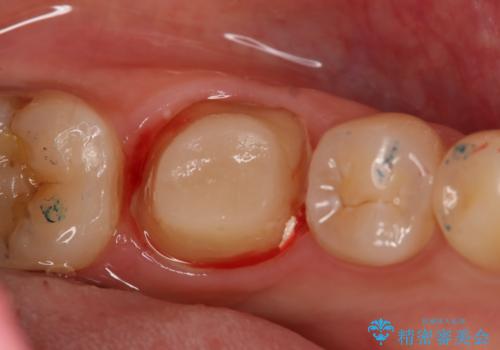

左下奥歯が腫れて痛い フルジルコニアクラウン

- 左下大臼歯の歯肉に腫れと痛みが繰り返し起こっているので治療を希望し来院された患者様です。

既に治療されている歯でしたが根尖部に病巣が確認出来たので、精密根管治療とクラウンの再治療が必要と判断されました。

精密根管治療を行なったことで病巣は消失し、腫れや痛みは再発することなく経過は良好です。

被せ物はフルジルコニアクラウンを選択されました。